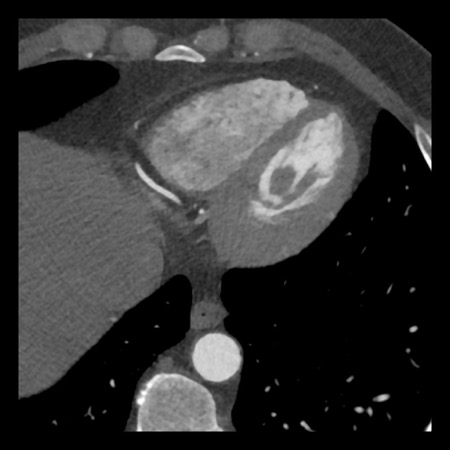

case 3 – Calcium score 0 and severe stenoses.

First, scroll through the CTA images.

How would you describe the findings on the coronary CTA?

The findings are:

- The total calcium

score of 0 indicates the absence of calcified plaque in the coronary

tree. - Severe stenosis

(70-99%) in the mid LAD and D2 branch.